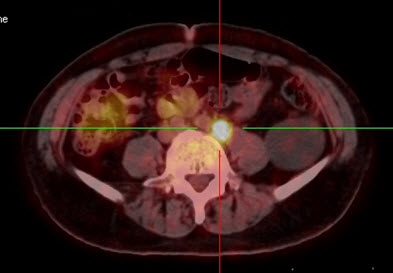

Mai Trọng Khoa và cộng sự đã tiến hành chụp 18FDG-PET/CT cho các bệnh nhân bị u lympho ác tính và nhận thấy các tế bào ác tính tại u nguyên phát và các tổ chức di căn hấp thu mạnh 18FDG và có sự chênh lệch rõ rệt hoạt độ phóng xạ của dược chất phóng xạ này so với các tổ chức xung quanh. Vì vậy 18FDG-PET/CT rất có giá trị trong chẩn đoán u nguyên phát và phát hiện các di căn của u lympho ác tính không Hodgkin với độ chính xác cao. Có thể thấy rõ hơn những nhận định trên qua các hình ảnh PET/CT của một số bệnh nhân u lympho ácc tính không Hodgkin tại Trung tâm Y học hạt nhân và Ung bướu, bệnh viện Bạch Mai.

Hình 5. Bệnh nhân Nguyễn X.T., nam, 58 tuổi. Chẩn đoán: U lympho ác tính không Hodgkin, giải phẫu bệnh: WF6. Hình PET cho thấy tổn thương ở phổi, hạch, xương, tuyến thượng thận hai bên (mũi tên). Hình CT và PET/CT cho thấy tổn thương tăng hấp thu FDG tại vị trí tuyến thượng thận hai bên (mũi tên), max SUV=11,34.